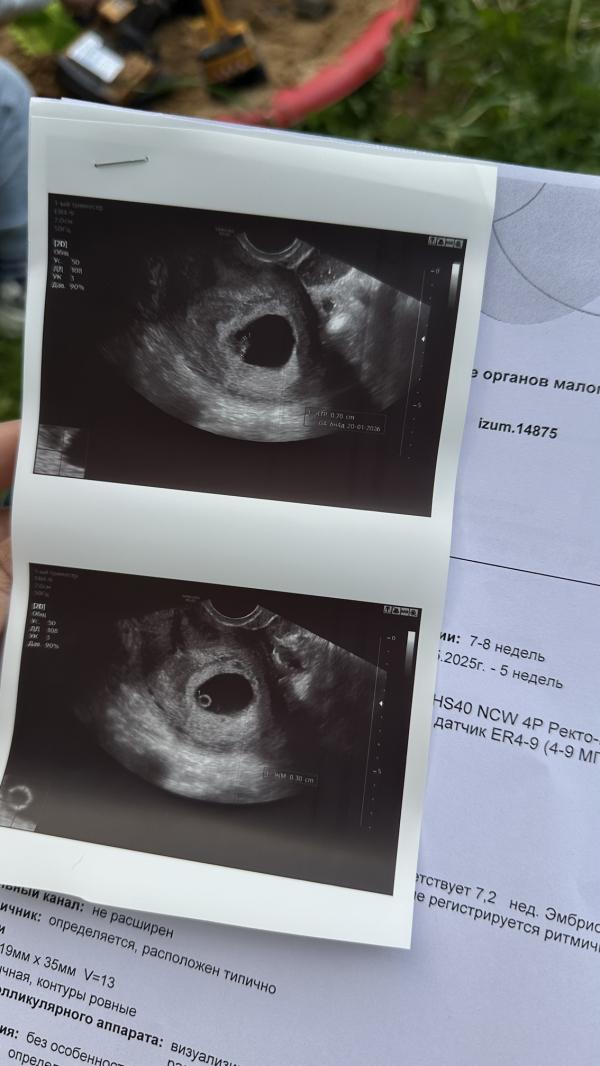

КТР 7 мм — это норма? Первые фото нашей фасолинки!

КТР 7мм

Фасолинка с сердечком 🥹❤️